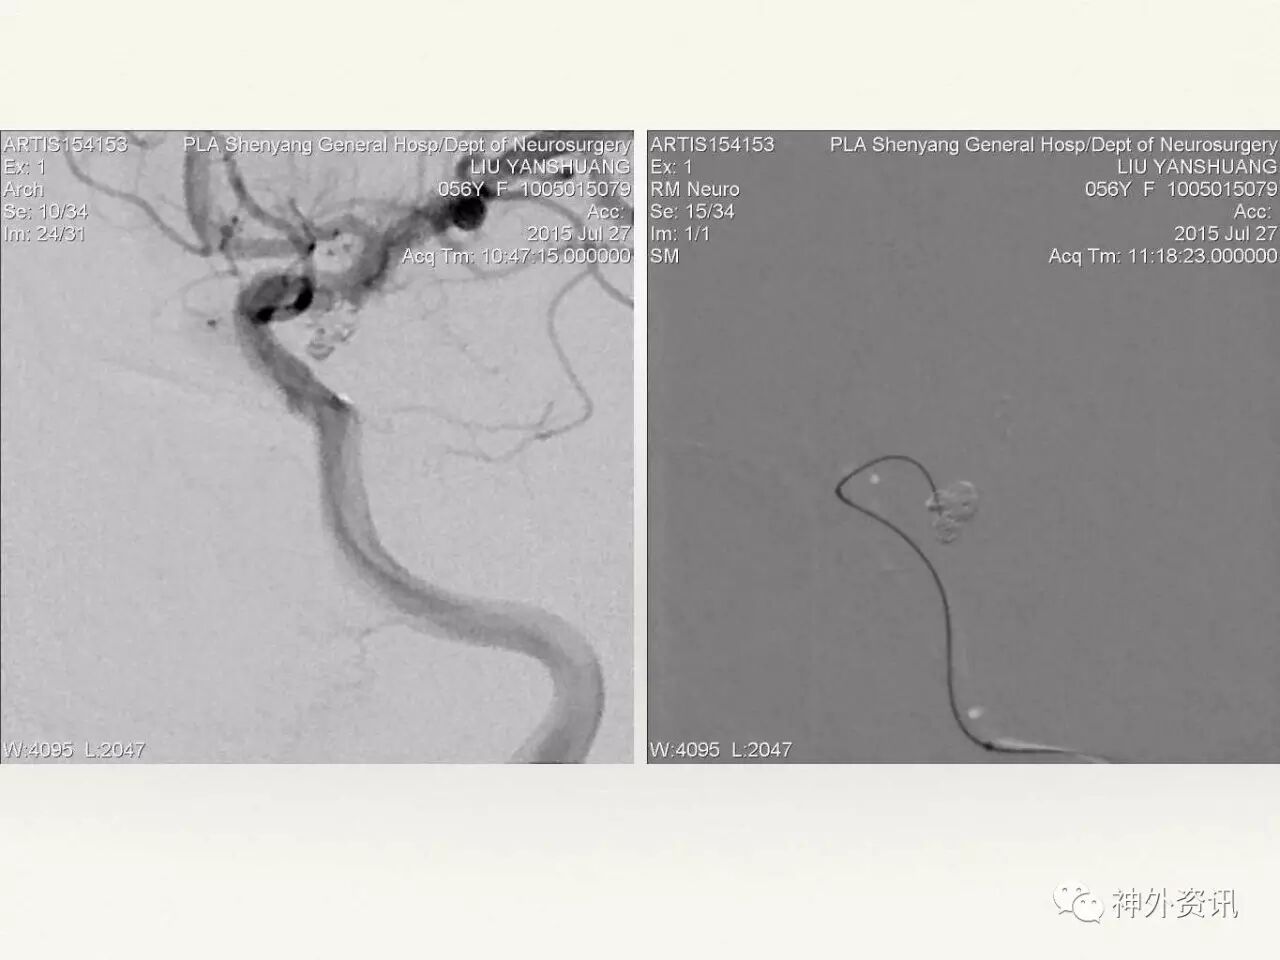

在东北地区率先开展了颈内动脉、大脑中动脉及基底动脉闭塞血管内再通、颅内动脉栓塞急性期取栓、血流导向装置治疗大型宽颈动脉瘤等,对颅内动脉瘤、动静脉畸形、颈动脉及颅内动脉狭窄、颈内动脉海绵窦瘘、硬脑膜动静脉瘘等外科治疗具有较深的造诣。完成脑血管造影8600余例,各类脑血管病介入手术共4500余例,动脉瘤、动静脉畸形、脑肿瘤、脑出血及脑外伤等外科手术1500余例。